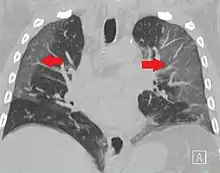

High-resolution CT image showing ground-glass opacities in the periphery of both lungs in a patient with COVID-19 (red arrows). The adjacent normal lung tissue with lower attenuation appears as darker areas.

COVID-19

CT image in patient with COVID-19 showing bilateral ground-glass opacities at the periphery of both lungs.

Ground-glass opacity is among the most common imaging findings in patients with confirmed COVID-19.[16][17] One systematic review found that among patients with COVID-19 and abnormal lung findings on CT, greater than 80% had GGOs, with greater than 50% having mixed GGOs and consolidation.[16] GGOs with mixed consolidation has most often been found in elderly populations.[18] Several studies have described a pattern among initial, intermediate, and hospital discharge imaging findings in the disease course of COVID-19. Most commonly, initial CT imaging reveals bilateral GGOs at the periphery of the lungs. During initial stages, this is most often found in the lower lobes, although involvement of the upper lobes and right middle lobe has also been reported early in the disease course.[16][18] This is in contrast to the two similar coronaviruses, SARS and MERS, which more commonly involve only one lung on initial imaging.[19][20] As the COVID-19 infection progresses, GGOs typically become more diffuse and often progress to consolidation.[11][18] This is sometimes accompanied by the development of a crazy paving pattern and interlobular septal thickening.[18] In many cases the most severe pulmonary CT abnormalities occurred within 2 weeks after symptoms began.[17] At this point, many individuals begin showing resolution of consolidation and GGOs as symptoms improve. However, some patients have worsening symptoms and imaging findings, with further increase in septal thickening, GGOs, and consolidation. These patients may develop lung "white-out" with progression to acute respiratory distress syndrome (ARDS) requiring treatment escalation.[17][21]

Preliminary reports have shown many patients have residual GGOs at time of discharge from the hospital. Due to the novelty of COVID-19, large studies investigating the long-term pulmonary CT changes have yet to be completed. However, long-term pulmonary changes have been seen in patients after recovery from SARS and MERS, suggesting the possibility of similar long-term complications in patients who have recovered from acute COVID-19 infection.[22]